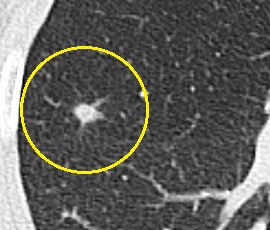

CT画像